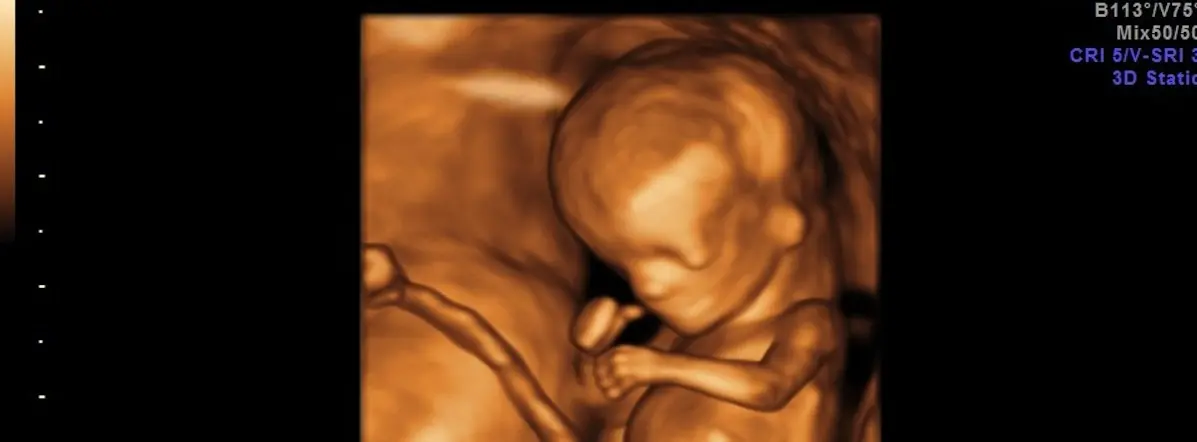

- Ultraschalluntersuchung: Dabei wird die Nackentransparenz (NT) des Kindes gemessen. Die NT ist der Flüssigkeitsraum im Nackenbereich des Fötus. Eine erhöhte NT kann ein Hinweis auf eine Chromosomenstörung sein. Zusätzlich wird das Nasenbein des Kindes betrachtet und die Blutflussmuster im Ductus venosus und an den Trikuspidalklappen beurteilt. Diese Informationen tragen zur Präzisierung des Risikos für Chromosomenstörungen bei.